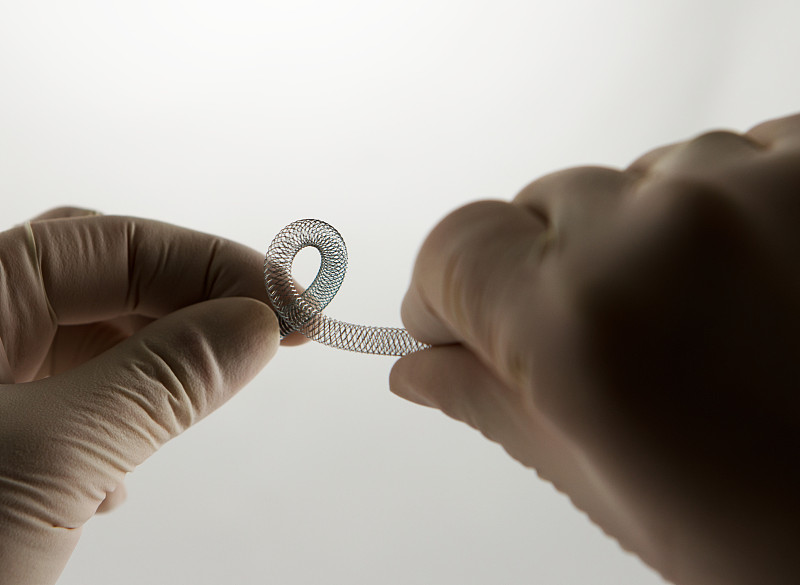

冠状动脉支架医疗详情

JPG

冠状动脉支架医疗详情

JPG

血管内手术支架,扭转详情

JPG